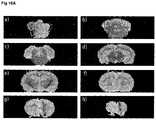

FIG. 16 T2weighted MRI images of (A) rapamycin-treated animals, (B) ketamine-treated animals and (C) control animals.